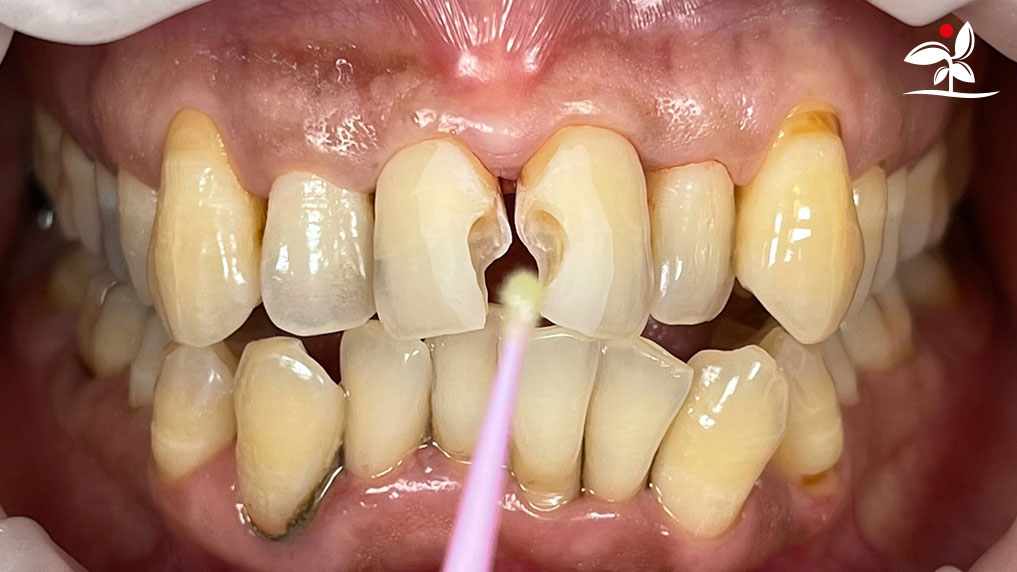

Restoration of Class IV Lesions using Naturomimetic Layering Technique (NLT) and Bioactive Restorative Materials

Dr Aung Pyae Phyo, Myanmar

With the growing awareness about the health, function and aesthetic benefits of preserving natural tooth structure, patients are now globally demanding for aesthetic dentistry with minimally invasive procedures that has a low biological cost. This public demand has encouraged logical clinicians to adopt to the minimally invasive cosmetic dentistry (MiCD) concept and its treatment protocol [1] in their practice. The author has been using MiCD concept and its treatment protocols since 2017, which

include the methods of treatment that are simple, fast, predictable and healthy. In aesthetic restoration, the tooth color restorative materials placement technique is one of the most challenging, confusing and frustrating areas to learn owing to the multiple techniques that have been proposed by many clinicians and replicating such techniques in practice is not always as easy as they are marketed in dentistry. Natural teeth are complex in structure and hard to simulate due distribution of colors through enamel and dentin [2]. Aesthetic restoration strategies should follow proper understanding of defects, right selection of restorative materials along with their proper application, finishing, texturing and polishing [2].